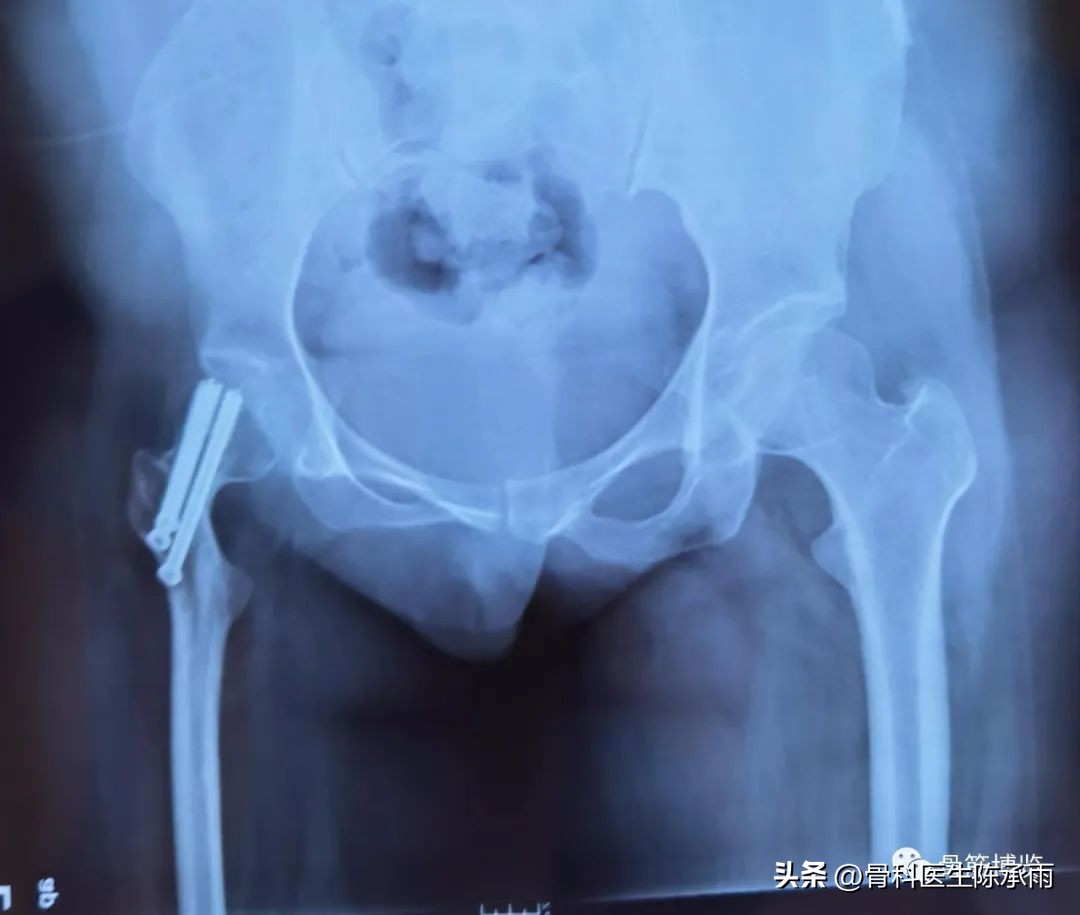

我们这例患者是一位脑瘫患者,患侧肢体短缩细小,股骨颈处及股骨髁上均做过截骨手术,失去了正常的角度,且股骨颈较细。给手术带来不小的难度。

术前尝试闭合复位,效果满意,决定行经皮穿钉,但股骨颈角度不正常,颈部细小,很难容得下3枚直径7.3空心钉,最后1枚空心钉部分切出股骨颈上缘。

术后拍片由于患肢内旋畸形,未显示标准正位